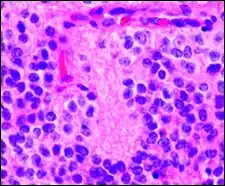

-

Micrograph of pineocytomatous/neurocytic pseudorosettes -

Histologic features of these two tumors are virtually identical, including their tendency to form neuropil-rich rosettes, referred to as pineocytomatous/neurocytic rosettes in central neurocytoma. Both are quite similar to the Homer-Wright rosette, but they are generally larger and more irregular in contour. The cells of the pineocytomatous/neurocytic rosettes are also considered to be much more differentiated than the cells forming Homer-Wright rosettes in that the nuclei are slightly larger, more rounded, much less mitotically active, and paler or less hyperchromatic. In rare cases, these rosettes may aggregate in a sheet of back-to-back clusters resembling fieldstone pavement.[2]